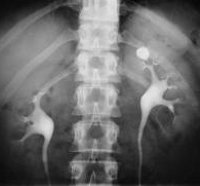

Ведущим методом выявления камней в почках служит рентгеновская диагностика. Большая часть конкрементов определяется уже при обзорной урографии. Однако белковые и мочекислые (уратные) камни почек не задерживают лучи и не дают теней на обзорных урограммах. Они подлежат выявлению с помощью экскреторной урографии и пиелографии. Кроме того, экскреторная урография дает информацию о морфо-функциональных изменениях в почках и мочевых путях, локализации конкрементов (лоханка, чашечка, мочеточник), форме и размерах камней в почках. При необходимости урологическое обследование дополняется радиоизотопной нефросцинтиграфией, МРТ или КТ почек.